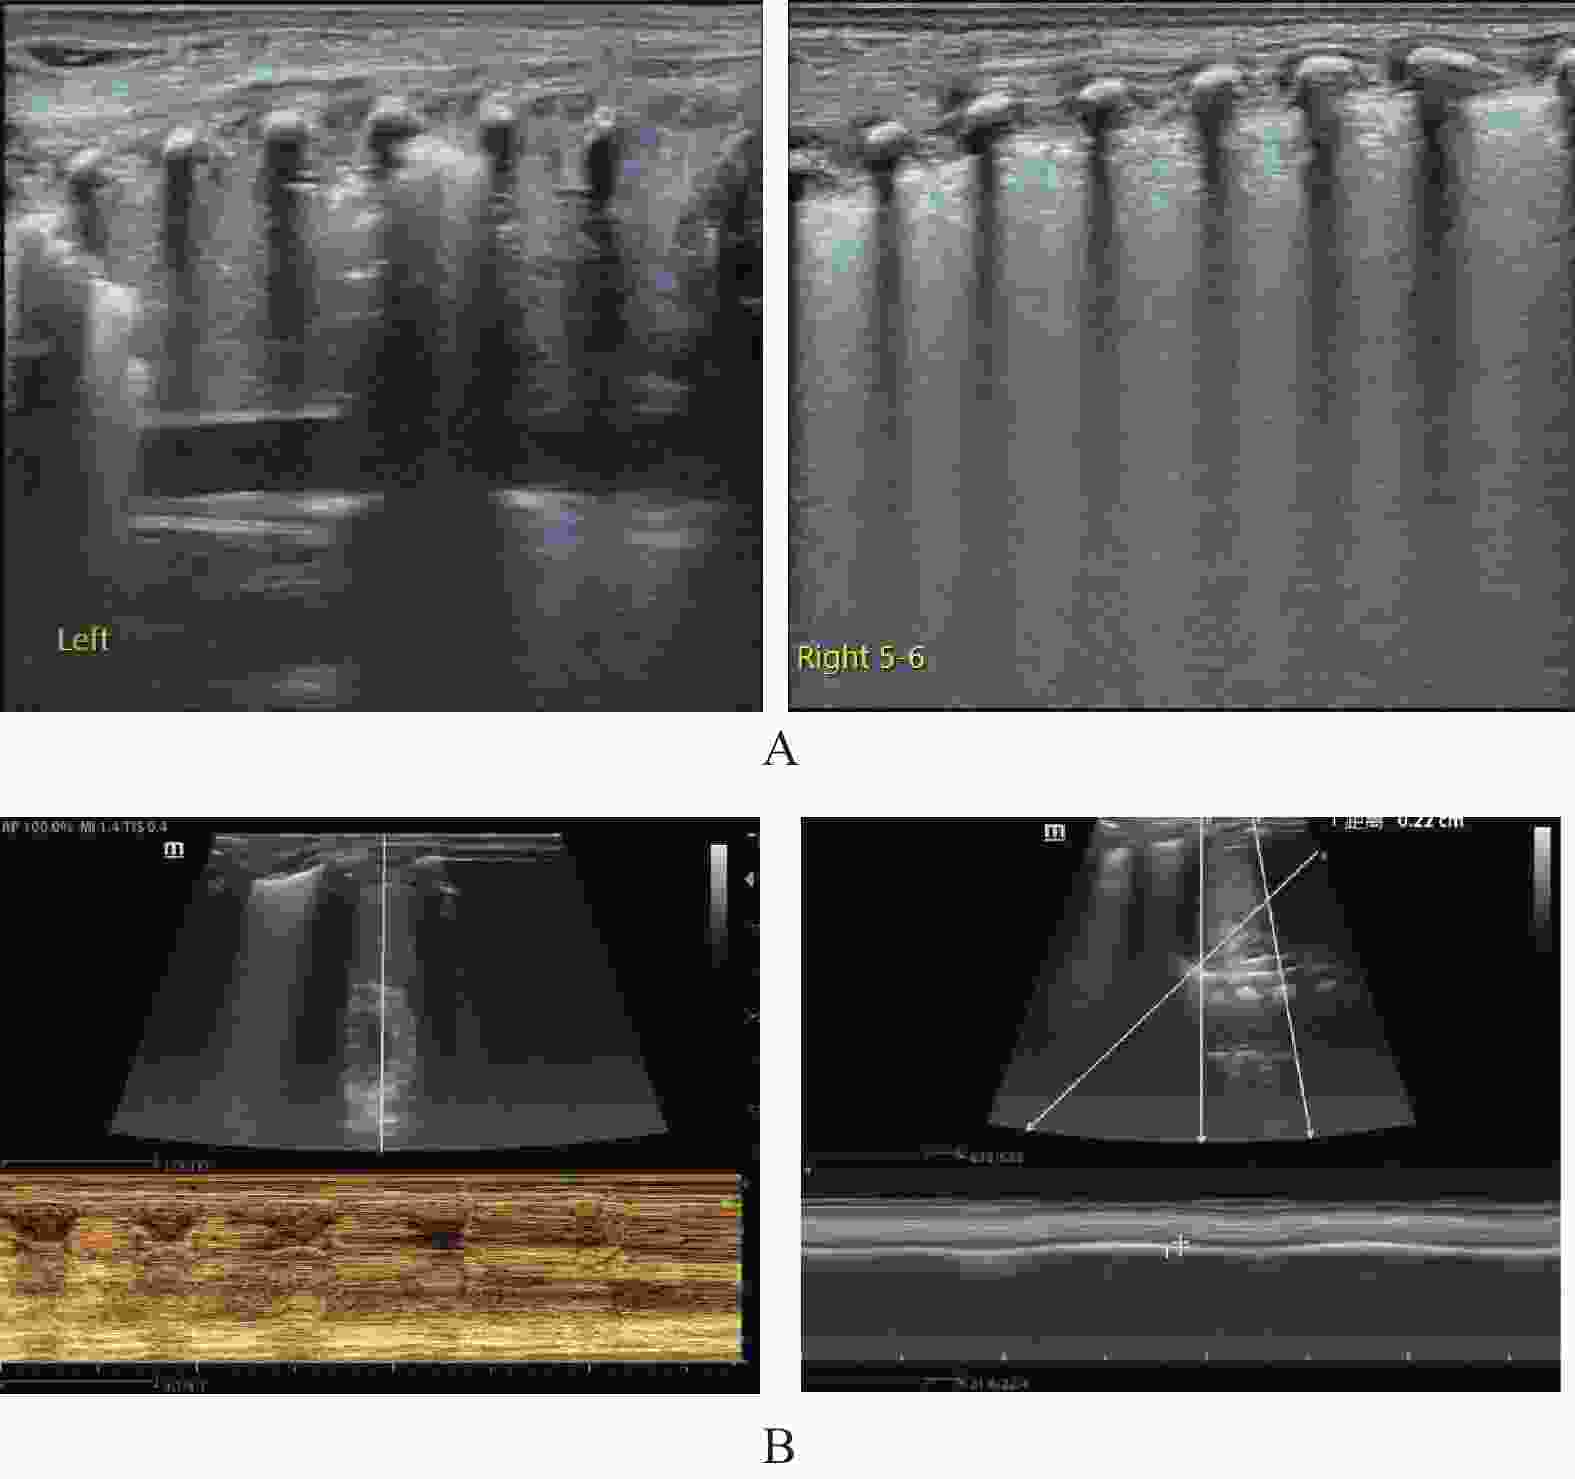

目的 探究肺部超声评分(LUS)、膈肌超声联合常规指标预测小儿重症肺炎(SP)并发急性呼吸窘迫综合征(ARDS)的价值。 方法 选取2022年8月至2023年8月昆明市儿童医院SP患儿160例,均行肺部超声、膈肌超声检查获取LUS、膈肌超声参数[膈肌移动度(DM)、膈肌厚度变化率(TF)],根据SP患儿住院期间是否并发ARDS分为ARDS组67例和非ARDS组93例,比较两组入院时一般资料、血清炎症因子水平、LUS、膈肌超声参数,分析SP患儿并发ARDS的影响因素,并分析LUS、膈肌超声参数预测SP患儿并发ARDS的价值。 结果 SP患儿住院期间ARDS发生率为41.88%(67/160);ARDS组入院时APS、APACHEⅡ评分、血清C反应蛋白(CRP)、白介素-6(IL-6)、高迁移率族蛋白B1(HMGB1)水平、LUS、DM高于非ARDS组,TF低于非ARDS组(P < 0.05);入院时APS、APACHEⅡ评分及血清CRP、IL-6、HMGB1水平、LUS、DM、TF均为SP患儿并发ARDS的影响因素(P < 0.05);LUS、DM、TF预测ARDS的曲线下面积(AUC)分别为0.718、0.742、0.720;常规预测方案(入院时APS、APACHEⅡ评分及血清CRP、IL-6、HMGB1水平联合)的AUC为0.852,新预测方案(常规预测方案基础上联合LUS、DM、TF)的AUC为0.930,新预测方案的AUC明显大于常规预测方案的AUC(P < 0.05)。 结论 LUS、膈肌超声参数DM、TF与SP患儿并发ARDS显著相关,联合常规指标可为临床预测SP患儿并发ARDS提供可靠依据。 Abstract:Objective To explore the value of lung ultrasound score (LUS) and diaphragm ultrasound combined with routine indicators in predicting the occurrence of acute respiratory distress syndrome (ARDS) in children with severe pneumonia (SP). Methods A total of 160 patients with SP were selected from Kunming Children’s Hospital from August 2022 to August 2023, all of whom underwent lung ultrasound and diaphragm ultrasound examination to obtain LUS and diaphragm ultrasound parameters [diaphragm mobility (DM), diaphragm thickness change rate (TF)]. The patients with SP were divided into ARDS group and non-ARDS group according to whether they were complicated with ARDS during hospitalization. The general data, serum inflammatory factor levels, LUS and diaphragm ultrasound parameters were compared between the two groups at admission, and the influencing factors of ARDS in children with SP were analyzed, and the value of LUS and diaphragm ultrasound parameters in predicting ARDS in children with SP was analyzed. Results The incidence of ARDS in SP patients was 41.88% (67/160). APS, APACHEⅡ scores, serum C-reactive protein (CRP), interleukin-6 (IL-6), high mobility group protein B1 (HMGB1) levels, LUS and DM in ARDS group were higher than those in non-ARDS group, TF were lower than those in non-ARDS group (P < 0.05). APS, APACHEⅡ scores, serum CRP, IL-6, HMGB1 levels, LUS, DM, TF were the influencing factors of ARDS in SP children at admission (P < 0.05). The area under the curve (AUC) of LUS, DM and TF predicted ARDS were 0.718, 0.742 and 0.720, respectively. The AUC of the conventional prediction scheme (APS, APACHEⅡ score combined with serum CRP, IL-6 and HMGB1 levels at admission) was 0.852, while that of the new prediction scheme (combined with LUS, DM and TF based on the conventional prediction scheme) was 0.930. The AUC of the new prediction scheme was significantly higher than that of the conventional prediction scheme (P < 0.05). Conclusion LUS, DM, TF, and SP parameters of the diaphragm are significantly correlated with ARDS in children with SP, and the combination of routine indicators can provide reliable evidence for clinical prediction of ARDS in children with SP. -

组别 n LUS(分) DM(cm) TF(%) ARDS组 67 20.15±3.26 1.41±0.34 37.24±3.65 非ARDS组 93 17.48±2.51 1.12±0.28 41.08±4.13 t 5.852 5.905 6.087 P <0.001* <0.001* <0.001* *P < 0.05。 表 3 SP患儿并发ARDS的影响因素分析